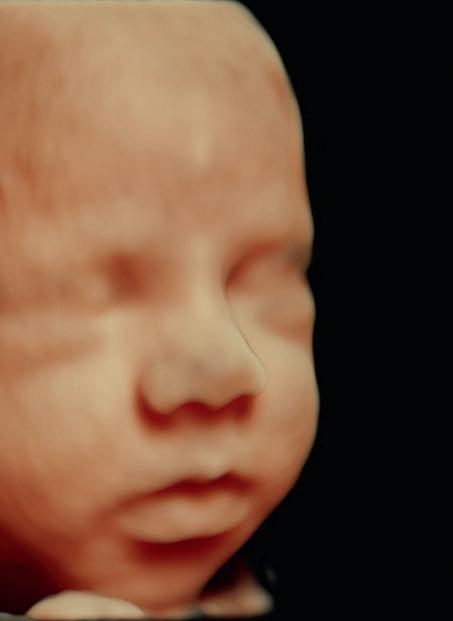

Ved en 3D-scanning får du en ekstra dimension med dybde. Det er en overfl adegenkendelsesteknik i ultralydsapparatet, som giver nogle utroligt naturtro billeder, der i langt højere grad svarer til at se sit barn i virkeligheden. Scanningsklinikken anvender udstyr fra GE, som bl.a. har HD-live, som giver en endnu flottere gengivelse end normal 3D-scanning. På den måde får forældrene indblik i, hvordan barnet ser ud med fine detaljer og personlige træk.

Dermed bliver det nemmere at knytte sig til barnet og f.eks. tale om, hvilke træk barnet har arvet fra henholdsvis mor, far eller en eventuel donor. Når barnet bliver mere virkeligt for forældrene, er det ofte også nemmere for dem at indføre livsstilsændringer, som kan gavne barnet.

Den fjerde dimension i 4D-scanningen er tiden. Det betyder, at 3D-billederne vises så hurtigt efter hinanden, at det ser ud som en film. Derfor er det bedst, at baby er vågen under en scanning, så der kan optages mange sekvenser med barnets bevægelser. Mens der scannes i 4D, kan I følge jeres barn live og f.eks. se, hvordan det smiler, smasker, gaber, sutter på fingre, rækker tunge osv.

Scanningsklinikken kan spole i sekvenserne og gemme de fineste dele af optagelsen samt gemme 3D-stillbilleder ud fra en 4D-sekvens. Med hjem får parret så både flotte 3D-billeder samt 4D-sekvenser.

"En 3D-scanning er som en præfødsel uden smerter og derfor en psykologisk forsmag på det allermest ømme, spændende og frygtindgydende, man kan stå over for i livet – nemlig det at blive forældre. Samtidig kan scanningen stille lidt af forældrenes enorme nysgerrighed ved at give et indtryk af, hvordan det her lille barn kommer til at se ud.“

"For kvinder, der bekymrer sig meget og har svært ved at slappe af under graviditeten, fx hvis de er vant til at kontrollere og skemalægge deres tilværelse, kan 3D-scanninger have en kolossal betydning, fordi det at se barnet før fødslen både beroliger og optimerer moderens intuitive kontakt til barnet i maven.“

"Dengang min kone og jeg ventede vores børn, var scanninger slet ikke en mulighed. Jeg synes, at det er fantastisk, at man i dag kan smugkigge til den lille. Hjemme hos os har vi været rigtig glade for at deltage i vores svigerdøtres graviditetsscanninger, og resultatet har vi hængende på køleskabet.“

"Det er et kig ind i den fantastiske proces, et voksende barn er. Samtidig giver det parret mulighed for sammen at skabe en fælles fortælling om barnet ud fra et så naturtro billede, som teknologien muliggør i dag. Det gravide par kan med billedet kigge ind i den verden, som venter dem.“

"Man siger, at følelser kun kan mærkes i nuet. 3D-scanningen er for manden en mulighed for at mærke, hvilke følelser der vil opstå i ham, når han ser sit barn ved fødslen. Det er en chance for at møde det konkrete barn og se, at det er virkeligt – før det bliver født.“

"3D-scanningen kan være en mulighed for at synkronisere manden og kvindens fortælling om graviditeten og forældreskabet. Billedet af barnet åbner i det hele taget op for fortællinger – også i forhold til parrets venner, familie eller barnets søskende. Samtidig kan billedet være en start på familiealbummet, fordi man med en 3D-scanning reelt kan se slægtens træk, og hvem barnet ligner – og det er den fortælling, der næsten altid går i gang allerede i de første timer efter fødslen.“